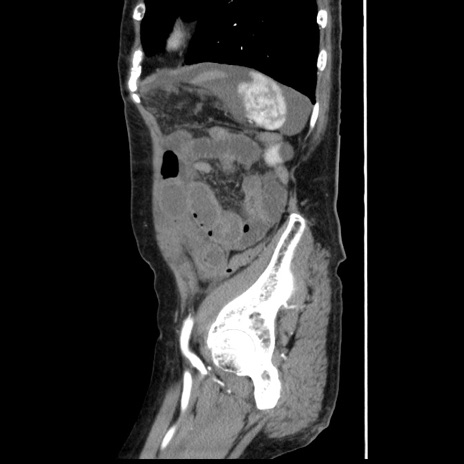

冠状断像

【症例】80歳代女性

【主訴】腹痛

【現病歴】8時間前から腹痛あり来院。

【既往歴】糖尿病、脂質異常症、子宮体癌にて子宮全摘術

【身体所見】意識清明・会話良好だが腹痛で苦悶様、全腹部にわたって反跳痛と圧痛あり

【データ】WBC 13600、CRP 0.14、LDH 224、CK 90